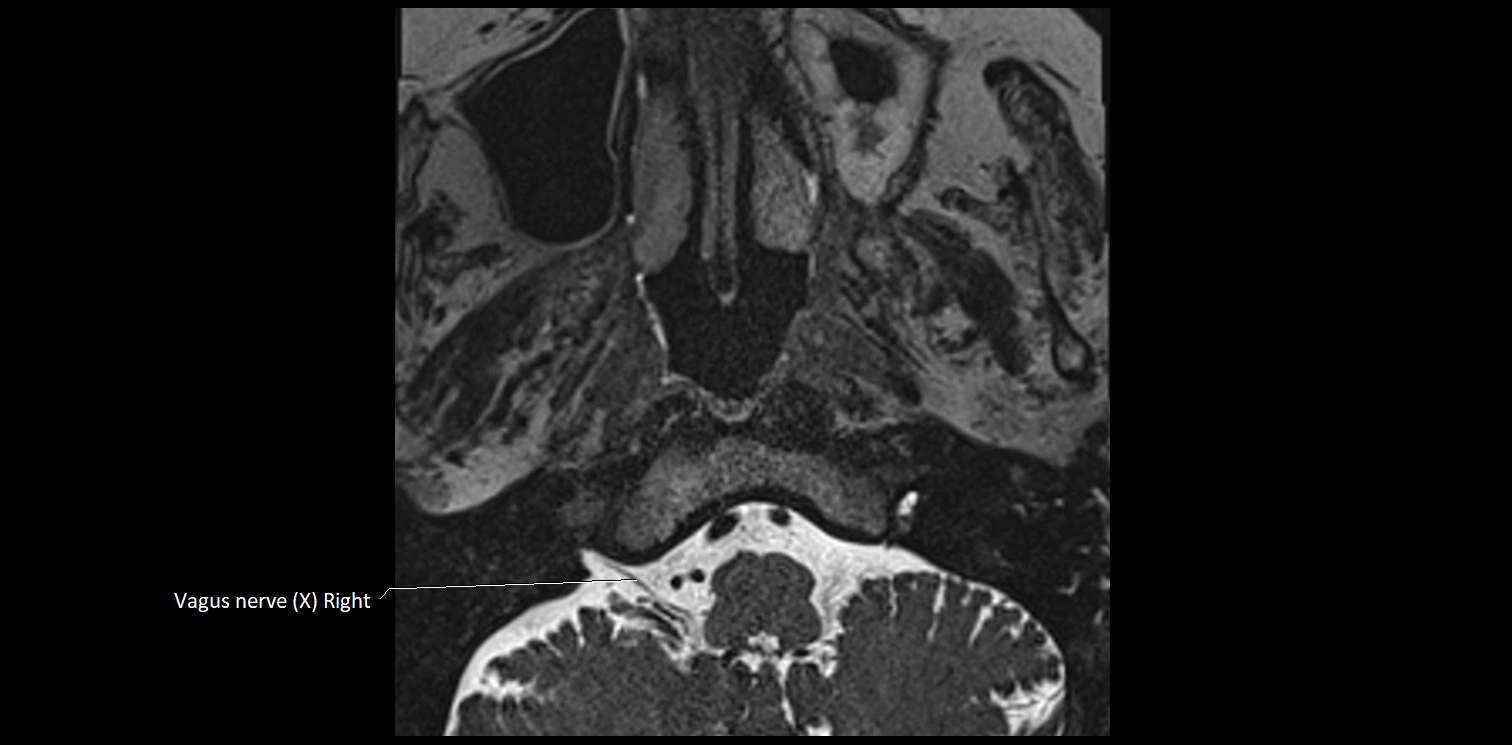

MRI images

image